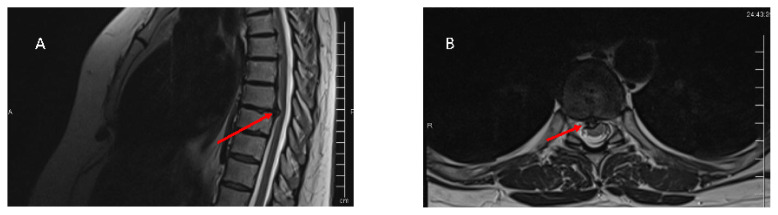

胸椎间盘突出(TDHs)是一种罕见的疾病,占所有报告的突出病例的0.1%至5%,并且在100万人中影响高达1人。胸椎中下段,特别是在T11和T12椎体之间,最常受影响,并常伴有创伤。像舒尔曼氏病这样的疾病会使患者易患TDHs。本研究探讨TDHs的临床表现、诊断方法、手术技术及并发症。诊断依靠磁共振成像和计算机断层扫描脊髓造影来确定水平和突出的性质。各种手术入路,包括后外侧、外侧和前路,都已实施,每种都有特定的适应症、优点和缺陷。并发症包括肺相关、神经系统恶化和硬脑膜破裂。临床表现主要包括胸背部疼痛。患者可表现出明显的神经功能障碍,这取决于疝的特点,即巨大的中央位置。手术干预是指在保守治疗失败或急性创伤明显压迫脐带。本综述旨在深入研究文献,为TDHs的临床表现、诊断、手术技术和相关并发症提供见解。

Thoracic disc herniations (TDHs) are rare conditions, comprising 0.1% to 5% of all reported herniation cases, and affecting up to 1 in 1,000,000 individuals. The mid to lower thoracic spine, particularly between the T11 and T12 vertebrae, is most frequently affected and often associated with trauma. Conditions like Scheuermann's disease can predispose patients to TDHs. This study explores the clinical manifestations, diagnostic methods, surgical techniques, and complications associated with TDHs. Diagnosis relies on magnetic resonance imaging and computed tomography myelography to identify the level and nature of the herniation. Various surgical approaches, including posterolateral, lateral, and anterior, have been implemented, each with specific indications, advantages, and pitfalls. Complications range from lung-associated to neurological deterioration to dural breaches. Clinical presentation primarily includes thoracic back pain. Patients can present with significant neurological deficits depending on the herniation's characteristics, namely giant centrally located. Surgical intervention is indicated in cases of failed conservative treatment or acute trauma with significant cord compression. This review aimed to delve into the literature to provide insights into the clinical manifestations of TDHs, diagnosis, surgical techniques, and associated complications.